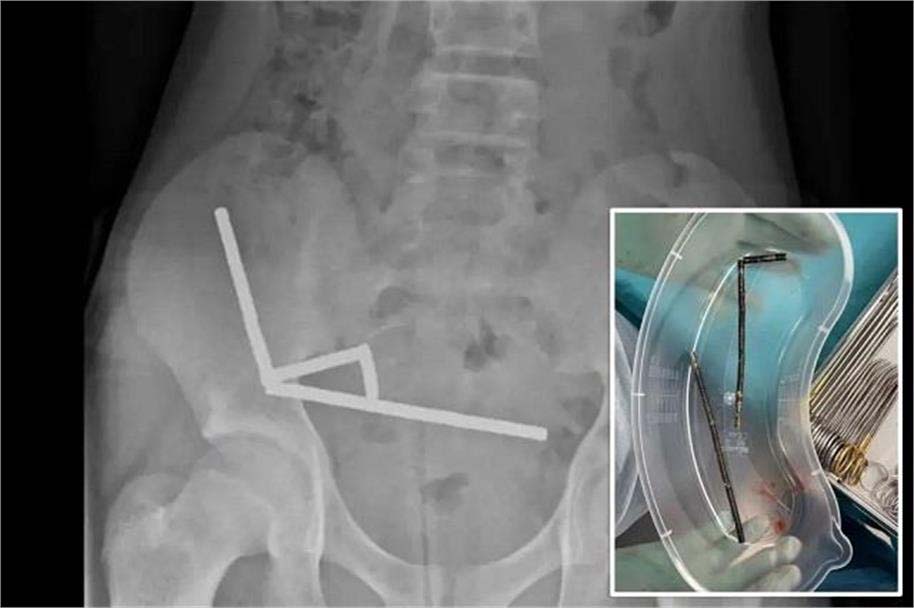

تیرہ سالہ لڑکے نے نگل لیے 200 مقناطیس، ناقابل برداشت پیٹ درد پر ڈاکٹروں نے بتایا خوفناک سچ